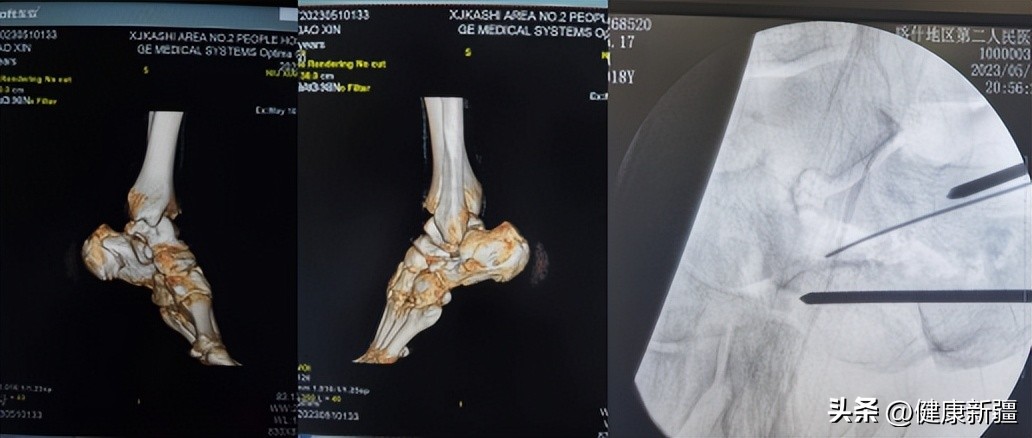

术中影像

术前,上海援疆专家、喀什二院骨科主任王建广带领骨科副主任项飞及骨科医护团队,结合患者CT等影像学检查及查体结果,制定了详细手术方案。手术采取了微创新疗法——跟骨粉碎性骨折经皮微创空心螺钉内固定术,即通过几个不到“1厘米”微创切口精细完成骨折的复位和固定。术中几乎没有出血,术后第二天即可开展康复训练,患者非常满意。